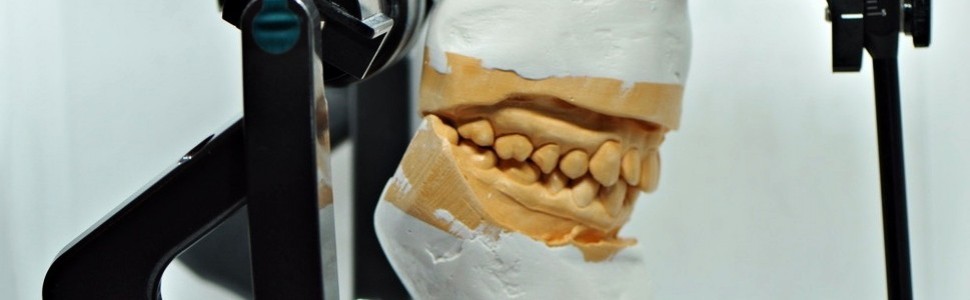

Po pewnym czasie ból powrócił – ząb zrobił się bolesny przy dotyku i nagryzaniu. Pacjentka wróciła do gabinetu, gdzie ponownie wykonano zdjęcie rentgenowskie, na którym przy wierzchołku korzenia dalszego była widoczna niewielka zmiana zapalna. Po przeprowadzeniu ponownego leczenia endodontycznego pacjentka nie odczuwała bólu przez kilka miesięcy, ale po pewnym czasie dolegliwości znowu powróciły. Ponieważ po wykonaniu zdjęcia pantomograficznego (ryc. 1) lekarz prowadzący doszedł do wniosku, że nie zna przyczyny problemu, pacjentka przyszła na konsultację do innego gabinetu. Po przeprowadzeniu wywiadu i badaniu wstępnym pobrano wyciski szczęki i żuchwy masą poliwinylosiloksanową w technice dwuwarstwowej w celu odlania modeli.

Po tygodniu pacjentka zgłosiła się na kolejną wizytę. Założono deprogramator Denar i pozostawiono pacjentkę na pół godziny z deprogramatorem w ustach. Po tym czasie w celu oceny stopnia deprogramacji mięśni żucia poproszono pacjentkę o powolne otwieranie i zamykanie jamy ustnej. Tor ruchu był prostolinijny, co pozwalało przypuszczać, że doszło do rozluźnienia napiętych podczas poprzedniej wizyty mięśni żucia i umożliwiło wykonanie trójstopniowego testu obciążenia stawów skroniowo‑żuchwowych przy pomocy rękoczynu Dawsona (4) (ryc. 7). Podczas rękoczynu Dawsona zadawano pacjentce pytania, czy nie czuje bólu w stawach skroniowo‑żuchwowych lub napięcia w mięśniach żucia. Test przebiegł bezbólowo i bez odczucia napięcia. Później pobrano trzy rejestraty zwarcia w relacji centralnej, używając do tego celu wosku Denar (ryc. 8). Następnie usunięto z jamy ustnej deprogramator przedni i stosując ponownie rękoczyn Dawsona, doprowadzono do pierwszego kontaktu zębowego, który, jak się okazało, był na guzku dalszym zęba 37. Pobrano rejestrację łukiem twarzowym, a otrzymane od technika modele oprawiono w artykulatorze (ryc. 9, 10). Do analizy zwarcia i planowania leczenia użyto łuku twarzowego Denar i artykulatora Denar Mark 320. Po opracowaniu w artykulatorze pierwszy punkt kontaktu międzyzębowego w relacji centralnej występował dokładnie w tym samym miejscu, co w jamie ustnej pacjentki – na guzku dalszym zęba 37. Po wykonaniu ekwilibracji ból ustąpił. Ten przypadek, jak i wiele innych, z którymi miałam do czynienia w czasie mojej pracy,

Ryc. 9. Modele oprawione w artykulatorze w relacji centralnej – kontakt występuje na guzku dalszym zęba 37 i zębie 27. Proszę porównać ze zdjęciem wykonanym w ustach pacjentki (ryc. 2) – w artykulatorze widoczna jest większa protruzja zębów siecznych górnych oraz większa szpara przednio‑tylna (czerwoną kropką zaznaczyłam kontakt międzyzębowy).